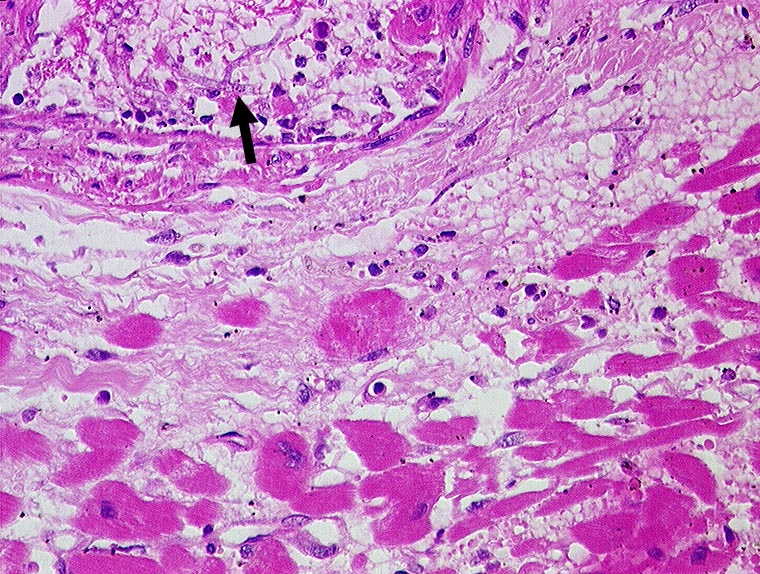

PathoPic ID 191 - Aspergillussepsis mit Myokardbefall

Aspergillussepsis mit Myokardbefall

►

Aspergillushyphen in einem intramyokardialen Gefäss.

Aspergillussepsis. Chronische lymphatische Leukämie. Metastasierendes Spinaliom.